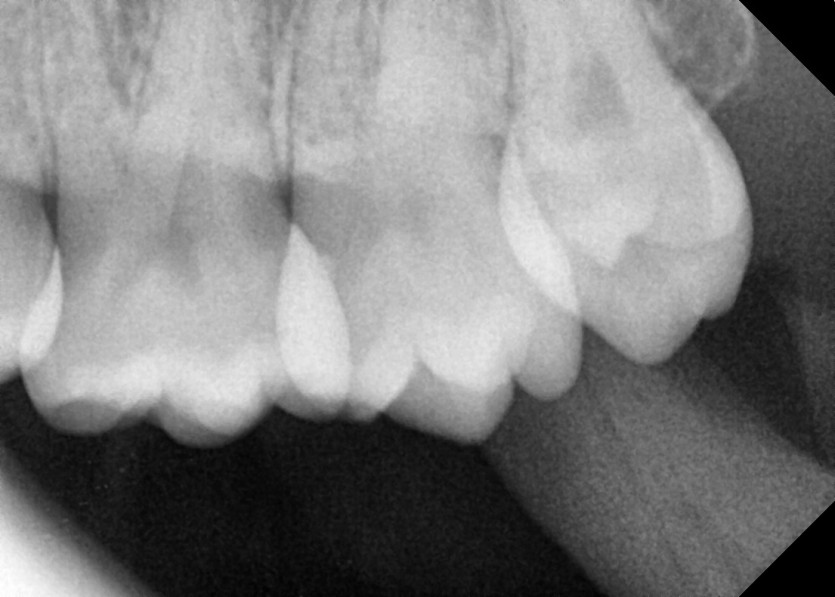

#28,38 사랑니 발치

구강 외과 전문의가 당일 발치했습니다.